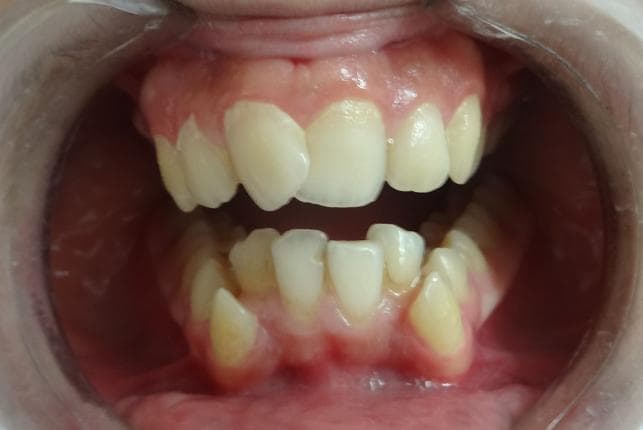

Hasta arka diste dolgu gecmisi oldugunu, ara ara cigneme hassasiyeti ve tekrar eden sizlamayi tarif etti.

- Dis yuzeyinin durumuna gore dolgu yenilemesi veya kanal tedavisi secenegi aciklandi.